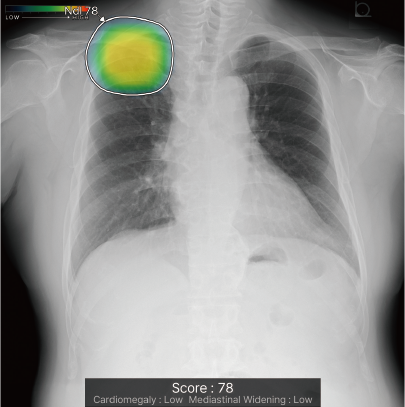

CXR-AIDが候補領域の解析をおこなったのち、0~100に応じた確信度を色分けして表示。

検出領域ごとに所見名を表示します。

対象所見のそれぞれの確信度の最大値が所見ごとに個別に表示されます。

ヒートマップと輪郭の表示は3パターンから選択可能です。